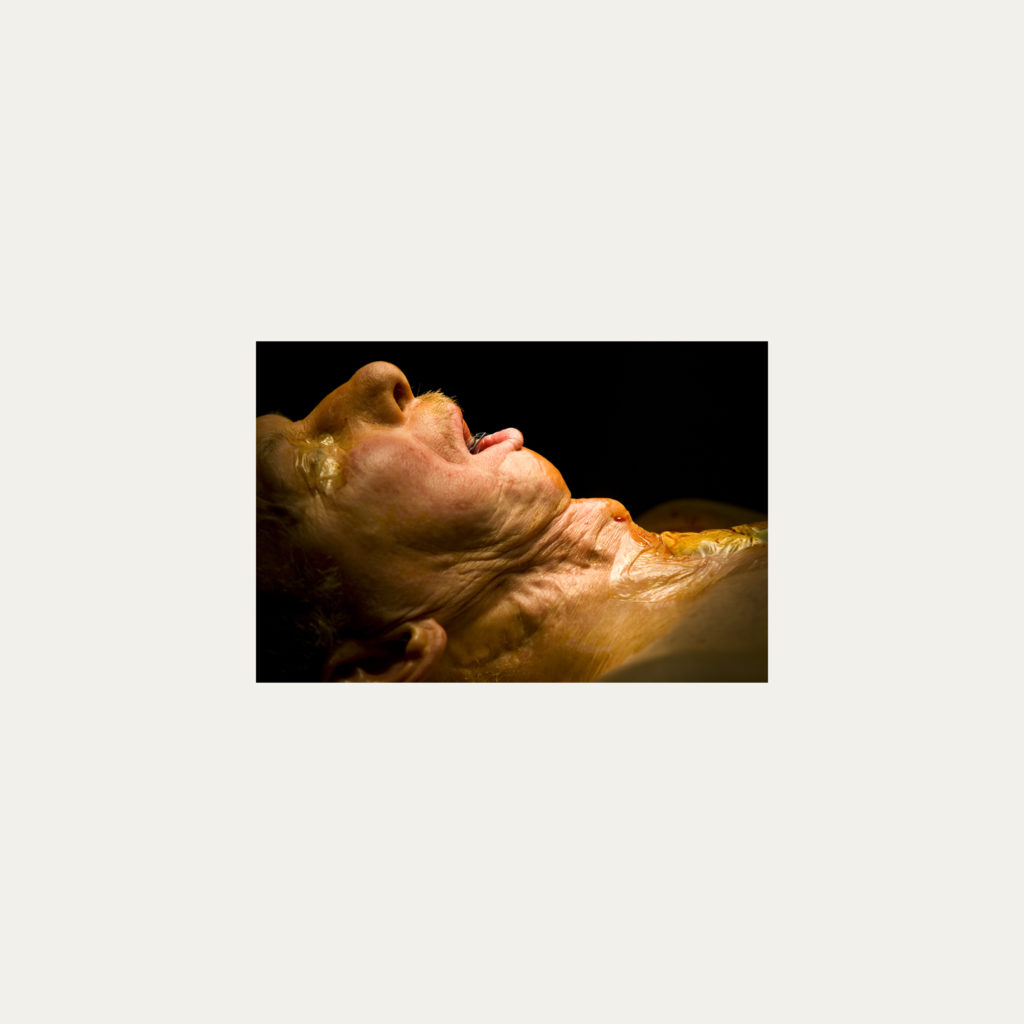

« Nature Morte » est la recherche de l’instant, pendant une intervention chirurgicale où la tête du patient opéré se retrouve seule dans le champ photographié. Aucune main intervenant, peu d’instruments chirurgicaux visibles, laissent le fragment de corps opéré existé pour lui-même. Les têtes, ainsi isolées, en deviennent presque des objets.

Cette approche est intensifiée par la présentation : dans de grands cadres carrés et passe-partout blancs, les photos de petit format font référence aux papillons épinglés de la collection d’un entomologiste.

Face à ces images, une forme de recueillement est nécessaire, s’approcher doucement pour s’approprier tous les détails des images.

Le caractère éminemment esthétique est souligné/donné par les gammes de couleur, la lumière précise sur la tête photographiée, les brillances partielles, renforçant également l’aspect pictural, les textures réelles.

L’humain présent dans ces images est celui qui rompt avec l’invisible et donne à voir l’architecture même de sa chair.